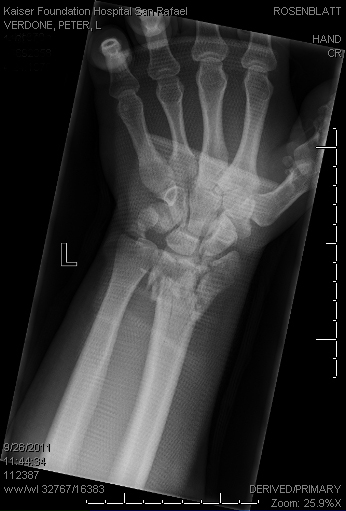

I got kicked off a big jump really bad on my warm up run. I flipped forward and landed head frist. Luckily, I didn’t break my neck. A concussion and a little swelling in my skull. I did, however, shatter my wrist. 6 peices of the radius. Sergery and 9 weeks in a cast for sure. Lot’s of new titanium bling.